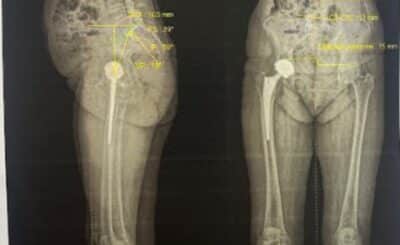

Avant une implantation de prothèse totale de hanche (PTH), la qualité de la planification chirurgicale conditionne direc...

Après la pose d’une prothèse de hanche, certains patients ressentent une impression d’inégalité de longueur entre les de...